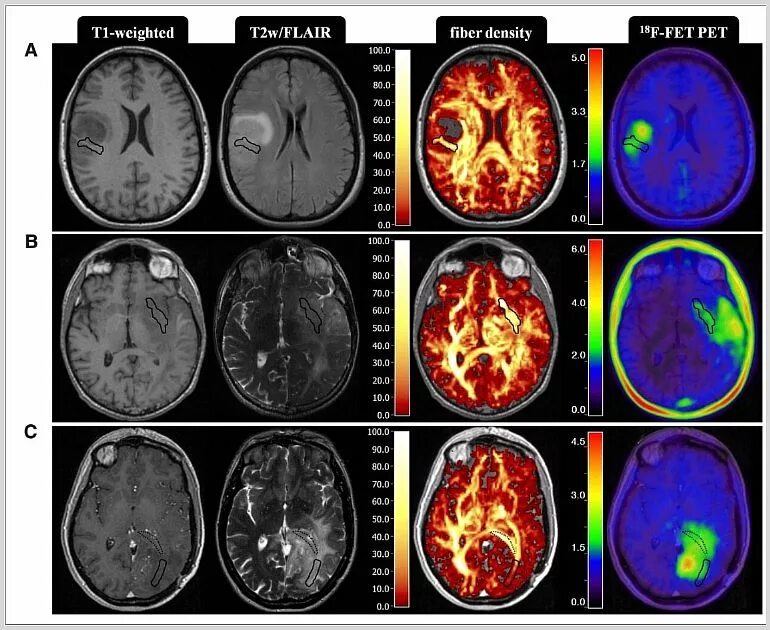

Стадии рака мозга симптомы